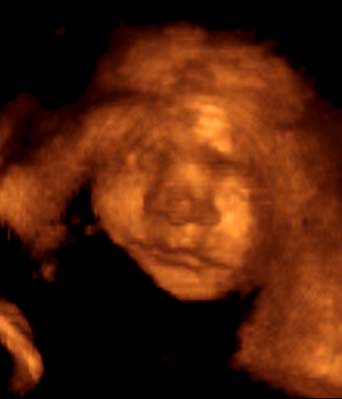

4D-ULTRAHANG

Fotógaléria / Arcok

A képeket Györfi Mátyás készítette.

26. hét

27. hét

29. hét

30. hét

31. hét